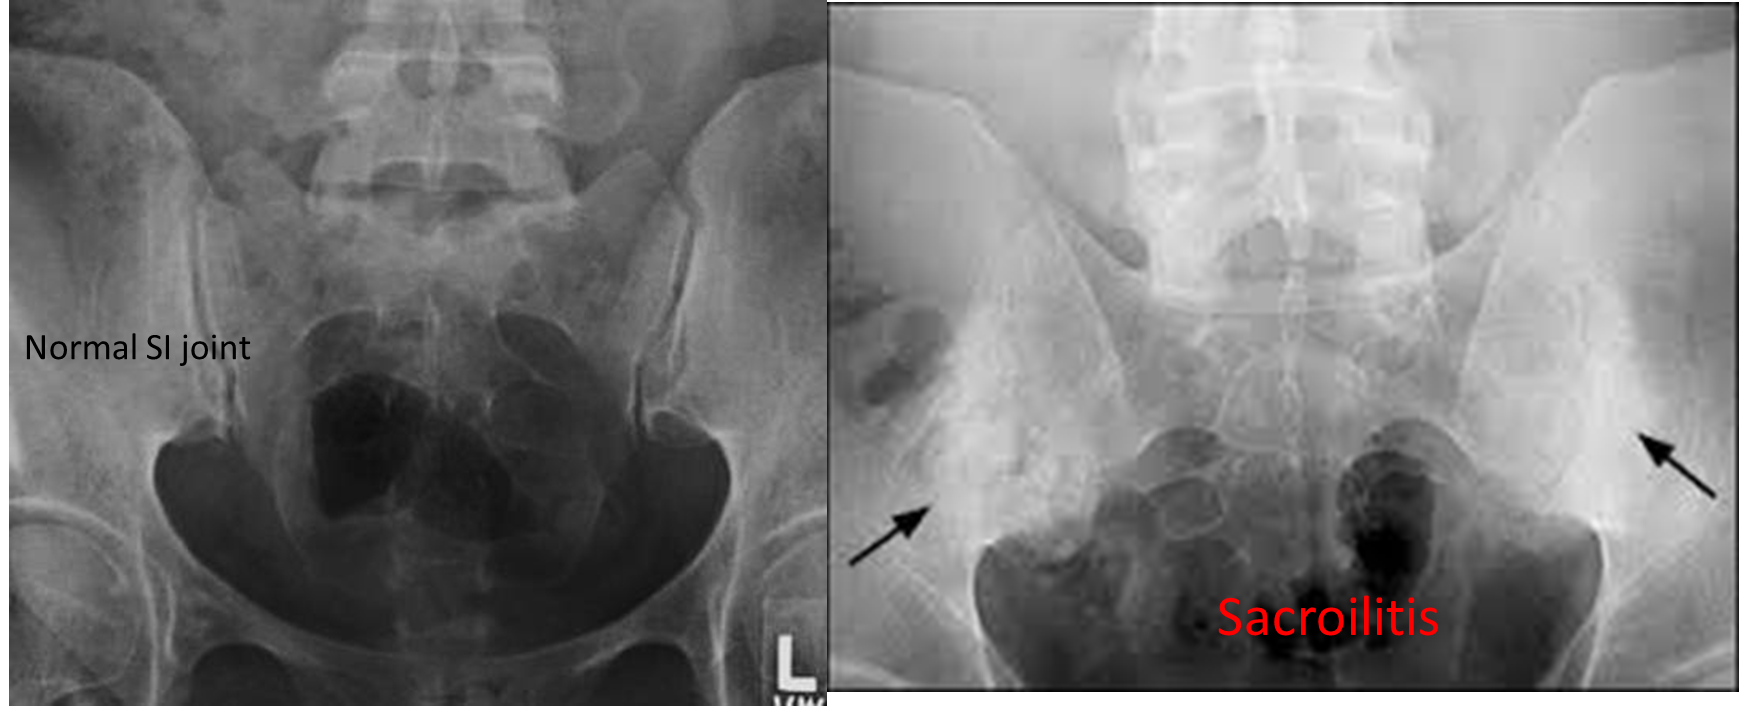

A. Sacroiliac joints (PA view) Characteristic findings (usually symmetrical) Signs of sacroiliitis; first sign: - Erosion and sclerosis of the sacroiliac joints

- Ankylosis: fusion of the articular surfaces